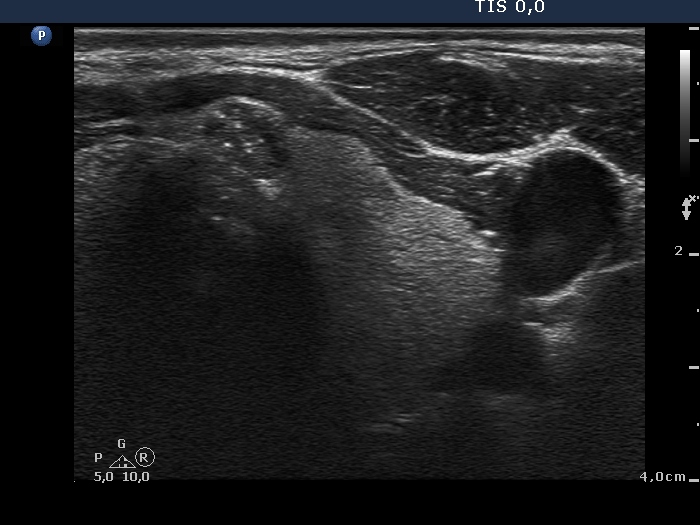

First examination (first to third rows of images):

Clinical presentation: A 26-year-old woman requested an evaluation of a nodule discovered by herself six weeks earlier.

Palpation: a hard, not freely moveable nodule in the lower pole of the left lobe.

Functional state: euthyroidism (TSH-level 1.76 mIU/L, FT4 15.2 pM/L).

Ultrasonography: The thyroid was echonormal. There were several hypoechogenic nodules presenting microcalcifications in both lobes and in the isthmus. There was a similar lesion under the lower pole of the left lobe. The vascularization of the lesions was variable.

Cytological diagnosis: papillary cancer from the lesion in the right, in the lower pole of the left lobe and under the lower pole of the left lobe.

Histopathology: multifocal, bilateral papillary cancer metastasizing to the lymph nodes in the left side of the neck. Diffuse, chronic lymphocytic thyroiditis was found outside the tumor.